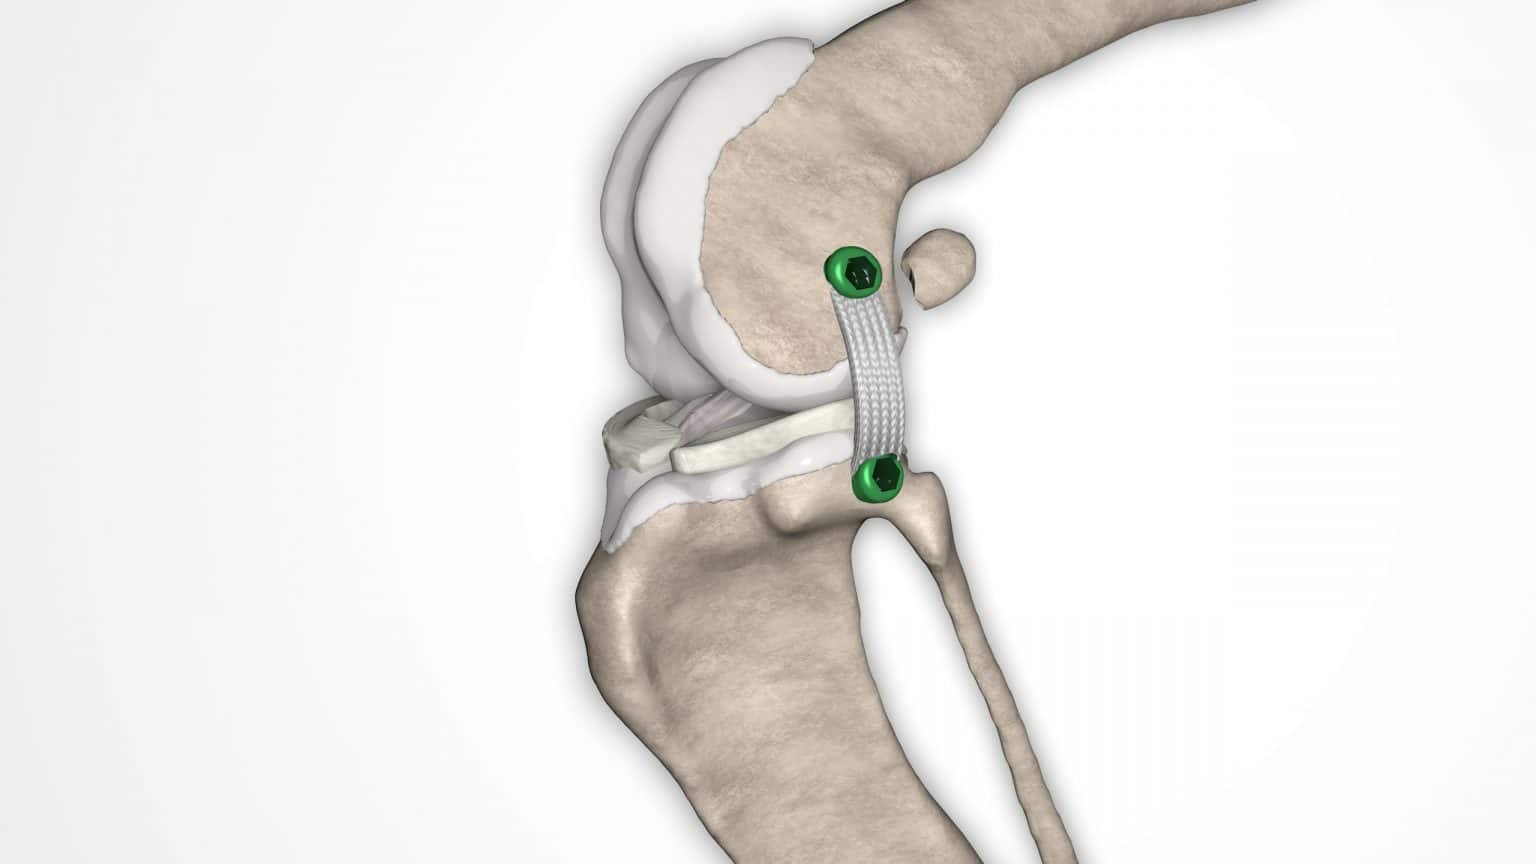

V případě ruptury kraniálního zkříženého vazu umožňuje ExtraTape® extraartikulární rekonstrukci co nejblíže izometrii původního vazu, čímž rychle a trvale stabilizuje koleno bez uzlů a zvlnění, což je slabina tradičnějších technik extraartikulární stabilizace. Ty jsou zde nahrazeny pevným ukotvením kosti pomocí interferenčního šroubu.

Řešení, které respektuje původní anatomii, obnovuje funkci postiženého vazu a je dostupné v rámci otevřené nebo artroskopické chirurgie.

NOVALIG® je syntetický vaz, který lze použít k rekonstrukci vazů a rychlému obnovení jejich fyziologických funkcí.

V případě zkřížených vazů umožňuje intraartikulární rekonstrukci v izometrických bodech připojení, čímž obnovuje biomechaniku kolene a všechny funkce natrženého vazu.